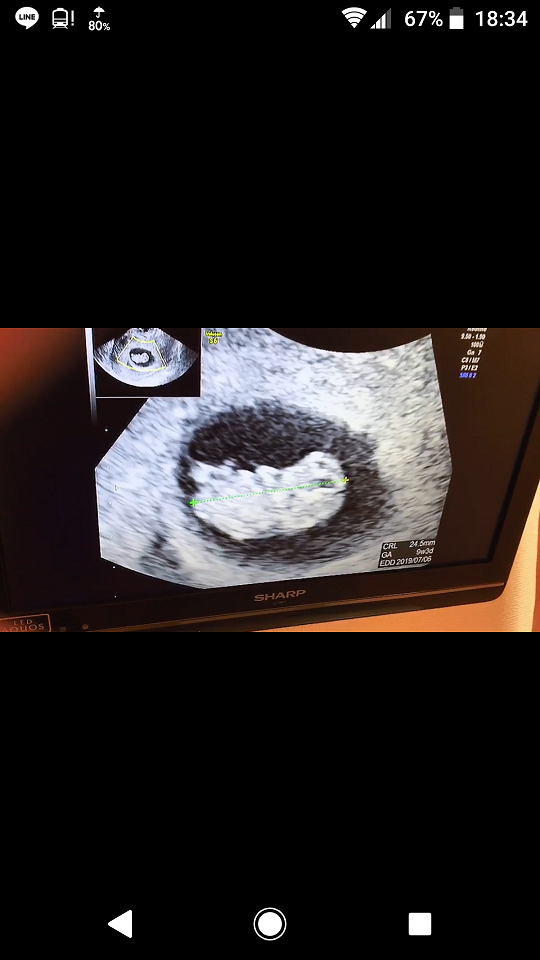

9週2日(9w2d・男の子)|Hubert さん(30歳)

エコー写真撮影時のエピソード:

待ちに待った赤ちゃんの様子がかわいらしくて感動しました。クリスマスの時期だったのでデコレーションをして、サプライズで夫の両親に報告しました。

義理母と義理父はうれしさのあまり大号泣で、産まれてくる前からみんなに歓迎されて愛されているのを実感しました。